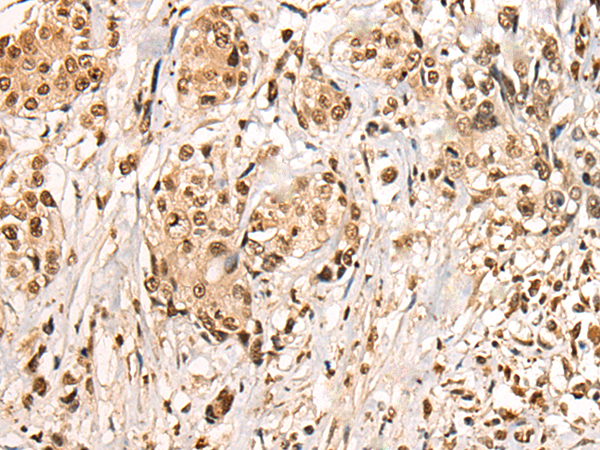

IHC positive control: |

Human prostate cancer |

IHC Recommend dilution: |

20-100 |